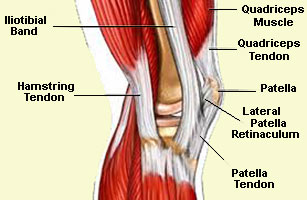

Iliotibial Band Syndrome

Running Injuries - Knee

Dislocated Kneecap

Also known as Patellar Subluxation Syndrome, this is where the kneecap moves out of its socket usually laterally to the outside

Patellofemoral Syndrome

This is probably the most common of running injuries, better known as runners knee! Pain is felt behind and around the knee cap, often on the outside edge, and you may experience a popping or grinding sensation. This happens because the knee cap does not move smoothly and centrally through the femoral groove. There will be little or no swelling despite the pain